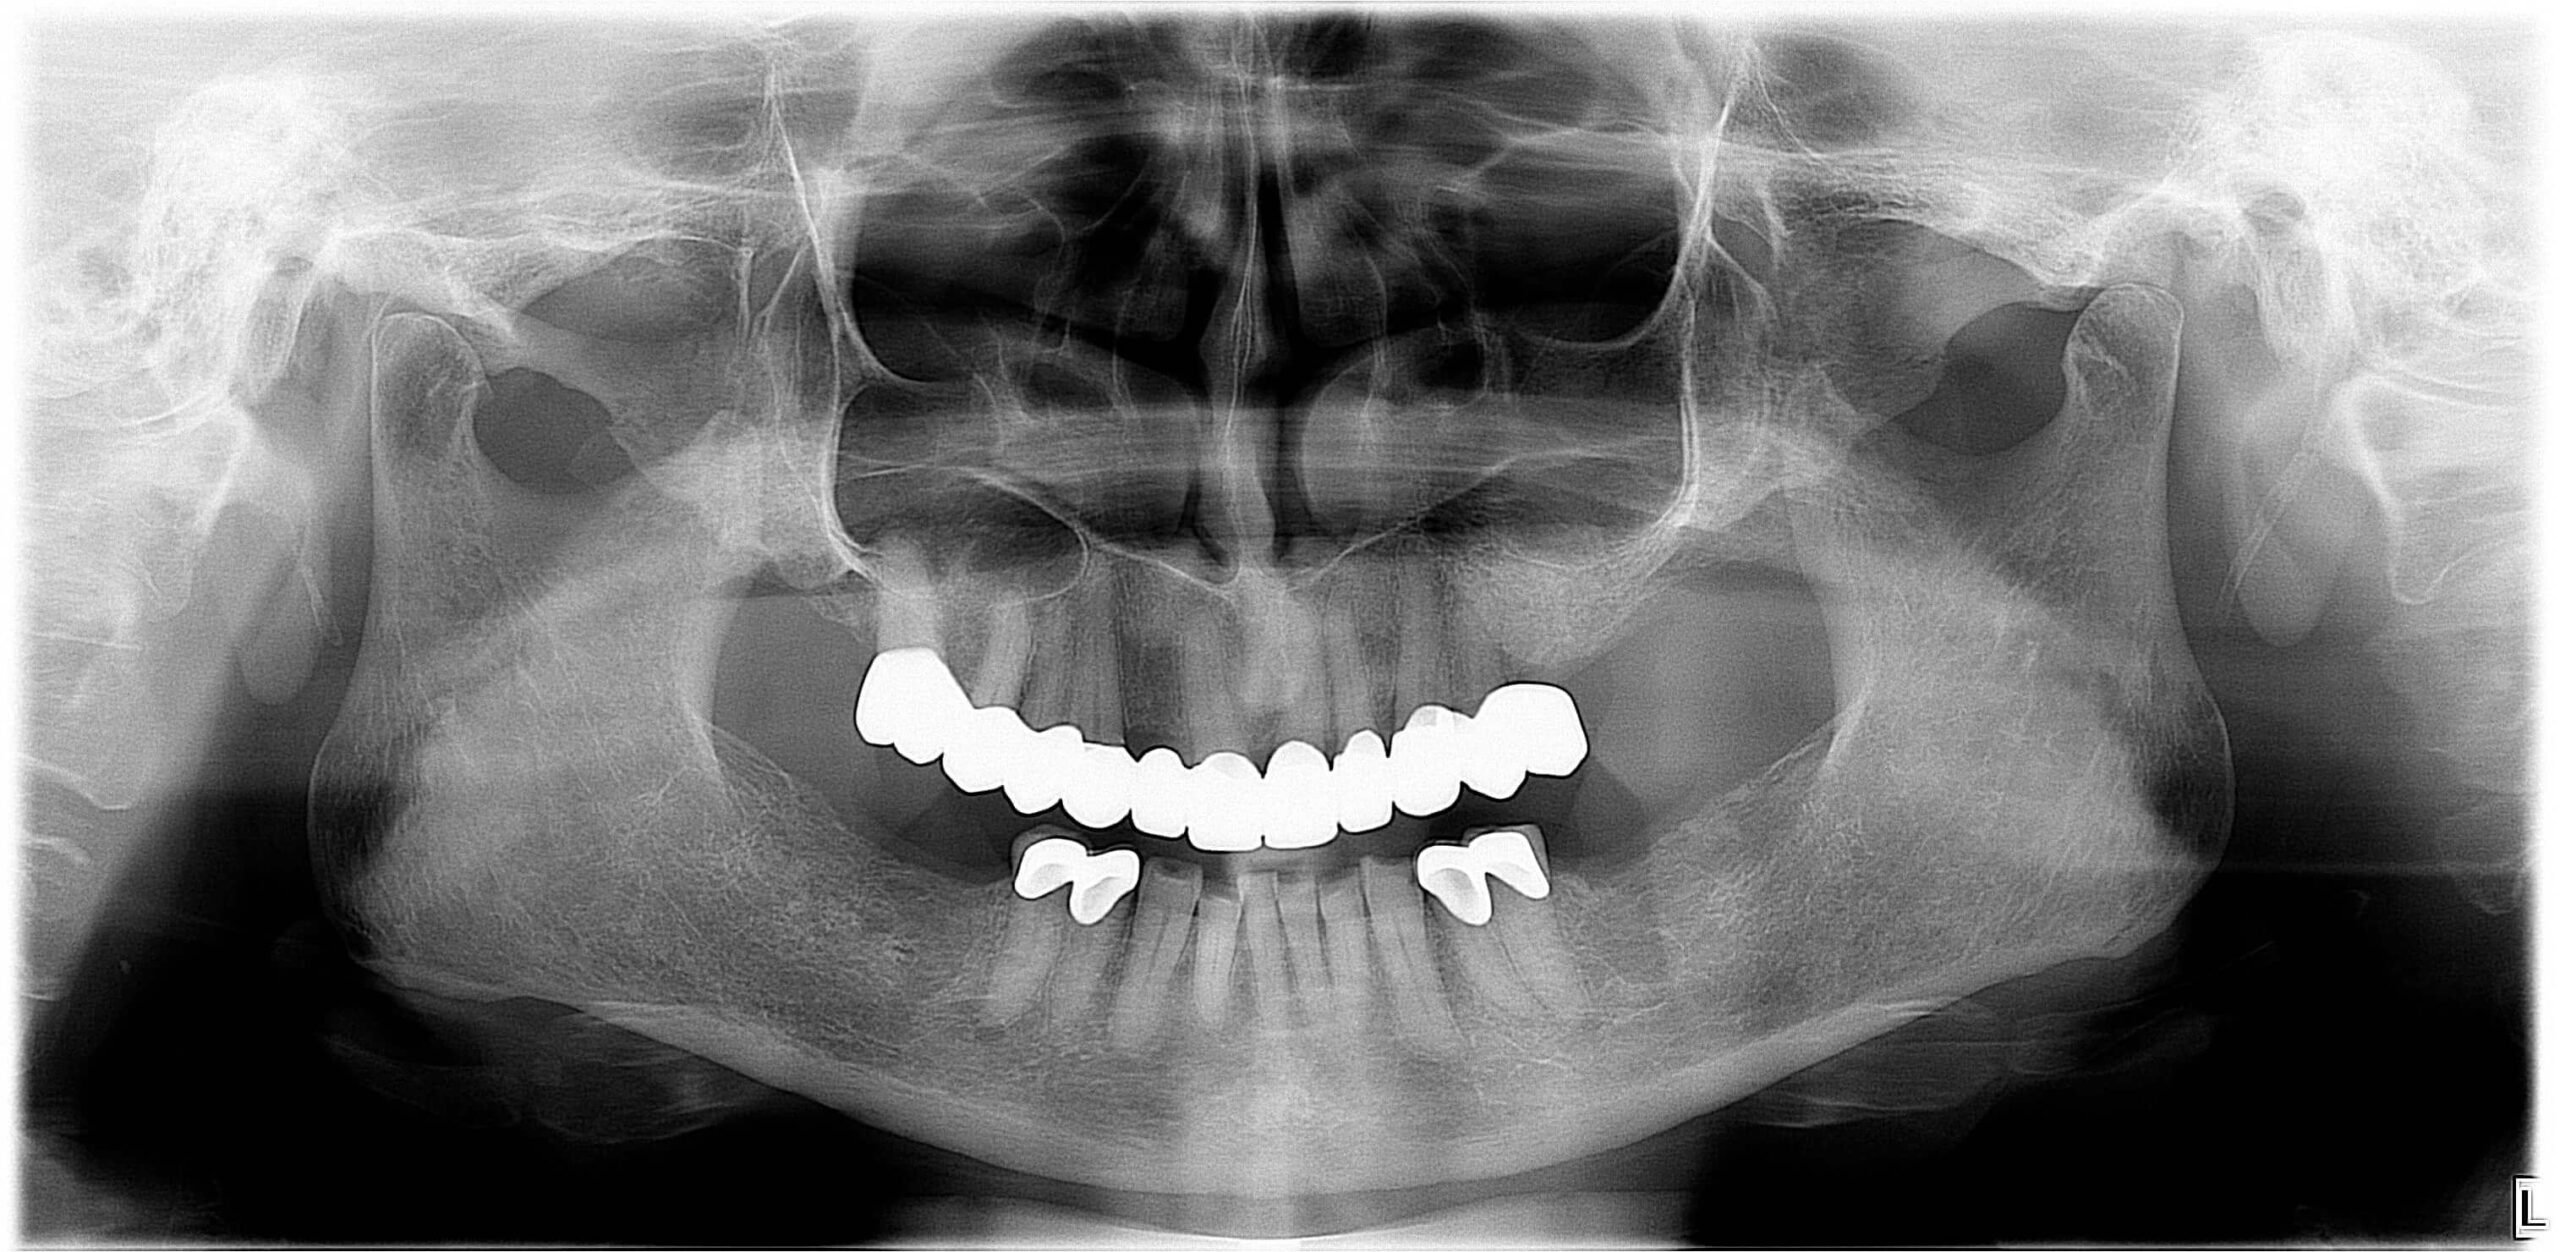

Egy PMMA próbát követően, kisebb esztétikai változtatásokkal a fogtechnikai labor elkészítette a full kontúr cirkónium pótlásokat, amelyek átadásra is kerültek. (6., 7. kép)

Az alsó metszőfogak szuvas és letöredezett részeit kompozit tömésekkel láttam el. (8., 9. kép)

Látványos végeredmény, biztató jövő